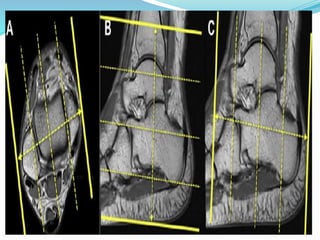

1- Sagittal ( T2 – T1 )

Plan the sagittal slices on the axial plane ;

angle the position block parallel to the medial and lateral

malleoli.

2- Axial T2

* Plan the axial slices on the coronal plane;

angle the position block parallel to the mortise joint .

* Check the positioning block in the other two planes.

3- Coronal ( T2 – T1 – STIR )

* Plan the coronal slices on the axial plane;

angle the position block perpendicular to the medial and lateral